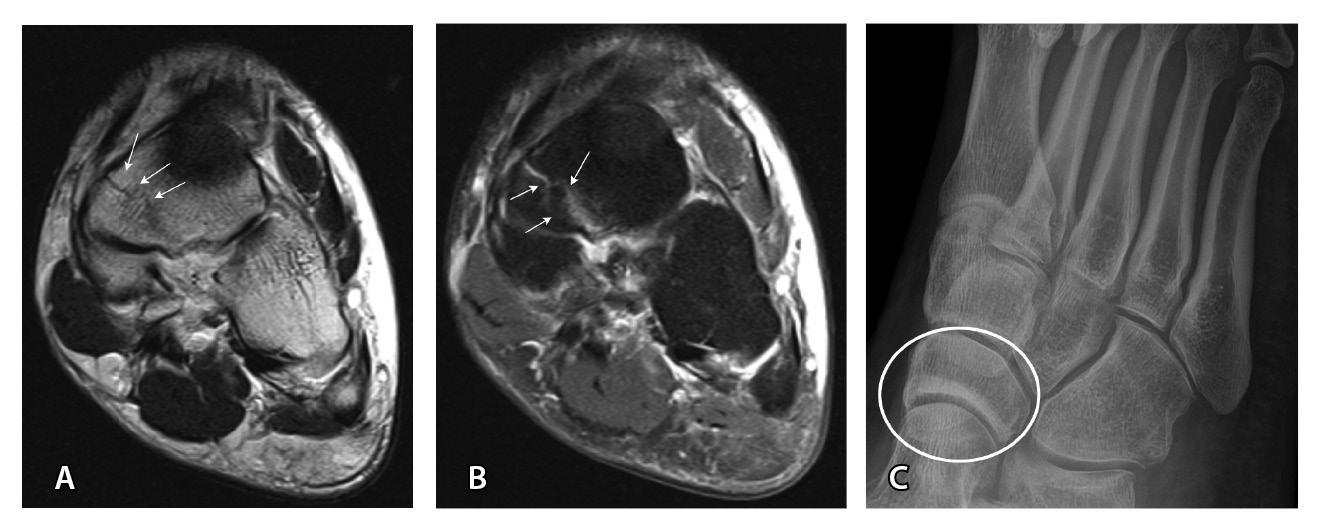

Важным условием для получения информативных МРТ-изображений является правильная укладка пациента и соблюдение стандарта сканирования: различия в натяжении или слабости связок при подошвенном или тыльном сгибании могут влиять на интерпретацию и приводить к ложноположительным или ложноотрицательным результатам [39, 52]. Магнитно-резонансное исследование выполняется лежа на спине с нейтральным положением голеностопного сустава и стопы. Рекомендации Европейского сообщества мышечно-скелетных рентгенологов 2016 г. (англ. European Society of Musculoskeletal Radiology, ESSR, 2016) по стандартному протоколу сканирования голеностопного сустава и костей предплюсны приведены в табл. 3 и на рис. 5 [56].

Рис. 5. Стандартный протокол магнитно-резонансной томографии голеностопного сустава согласно рекомендациям ESSR (2016): А – COR FS, Б – AX FS, В – COR T1, Г – SAG T1, Д – AX PD, Е – SAG STIR; AX – аксиальная, COR – корональная, FS – жироподавление, PD – протонная плотность, SAG – сагиттальная, STIR – инверсия-восстановление спинового эха